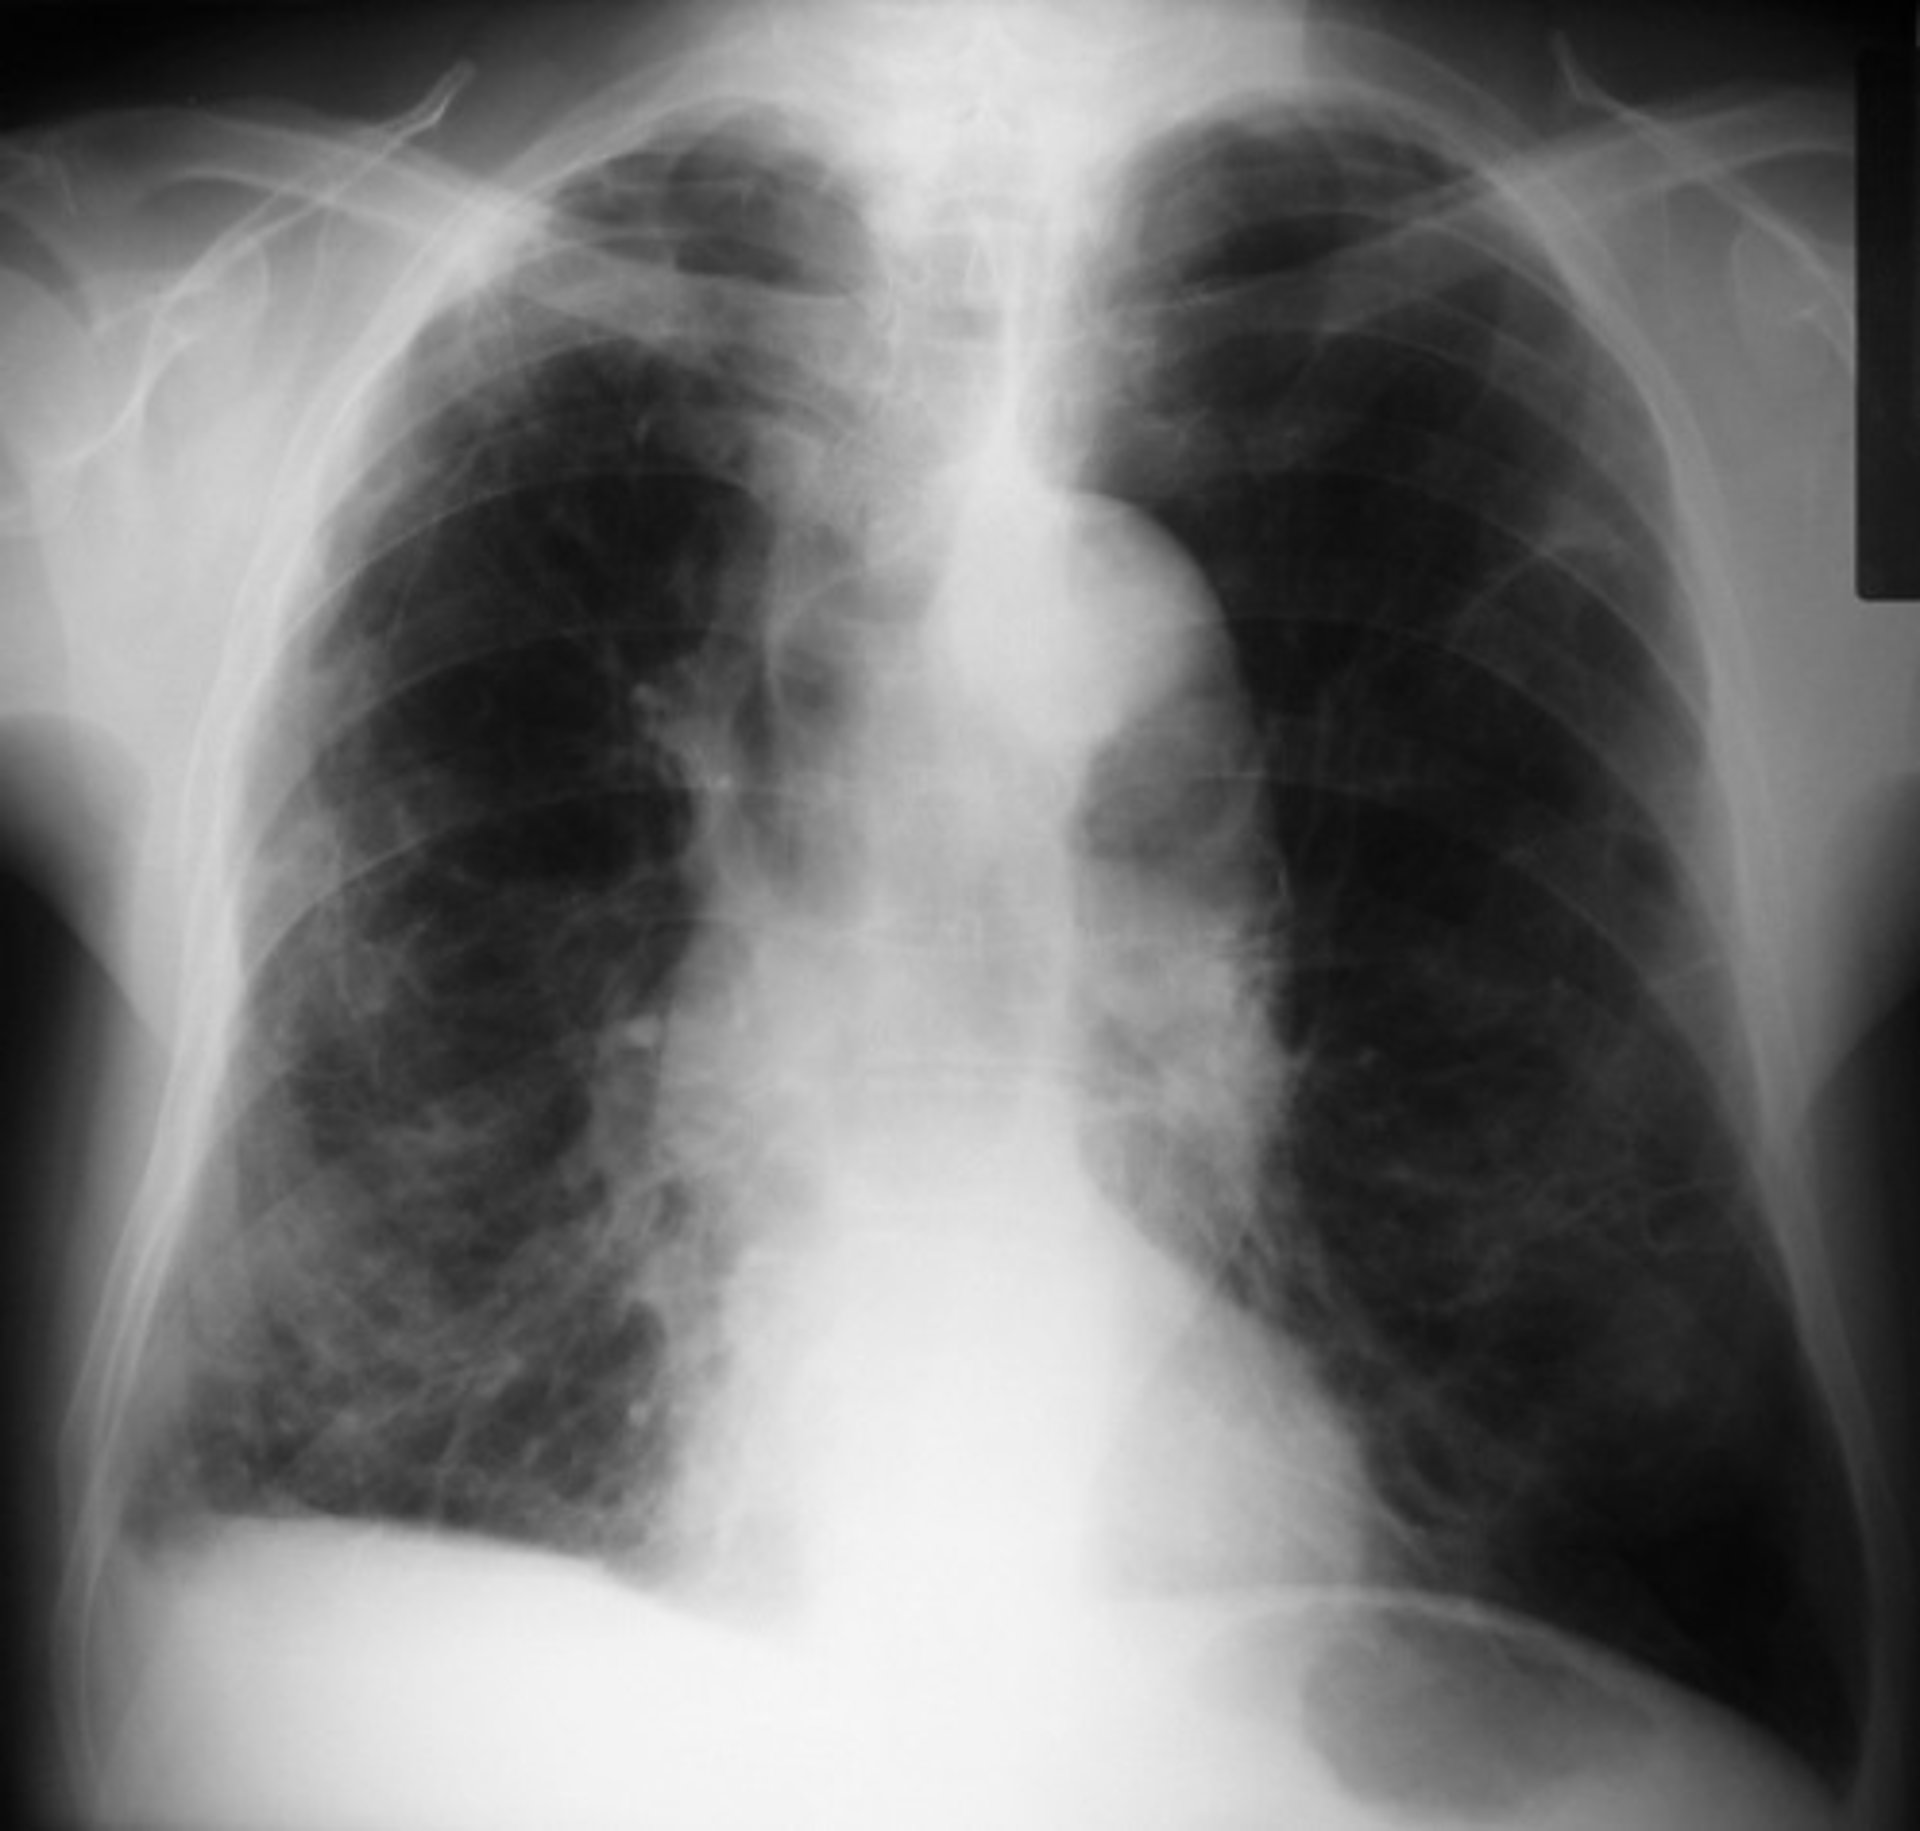

Los casos de EPOC crecen un 38% en España, según un estudio internacional

Las cifras de la EPOC o enfermedad pulmonar obstructiva crónica en España han crecido un 38 por ciento según los datos del estudio internacional Global Burden of Disease (GBD 2015), que sitúa el número de casos en 2,9 millones en 2015 frente a los 2,1 millones en 2007 del estudio EPISCAN.

Estos datos, dados a conocer por la Sociedad Española de Neumología y Cirugía Torácica (SEPAR), con motivo de la celebración este miércoles del Día Mundial de la EPOC, muestran la gravedad de una enfermedad que ya es la cuarta causa de muerte en España, con una estimación de 29.000 defunciones anuales, y que supone un ascenso del 61% respecto a las 18.000 defunciones anuales antes contabilizadas.

Según el estudio GBD, la EPOC figura entre las diez primeras causas de mortalidad y discapacidad combinadas. Representa así el 6,95% de las defunciones en el país por detrás de la cardiopatía isquémica (14,5%), el Alzheimer y otras demencias (13,6%), y el ictus (7,1%), y es más mortal que el cáncer de pulmón, que figura como la quinta causa de muerte.